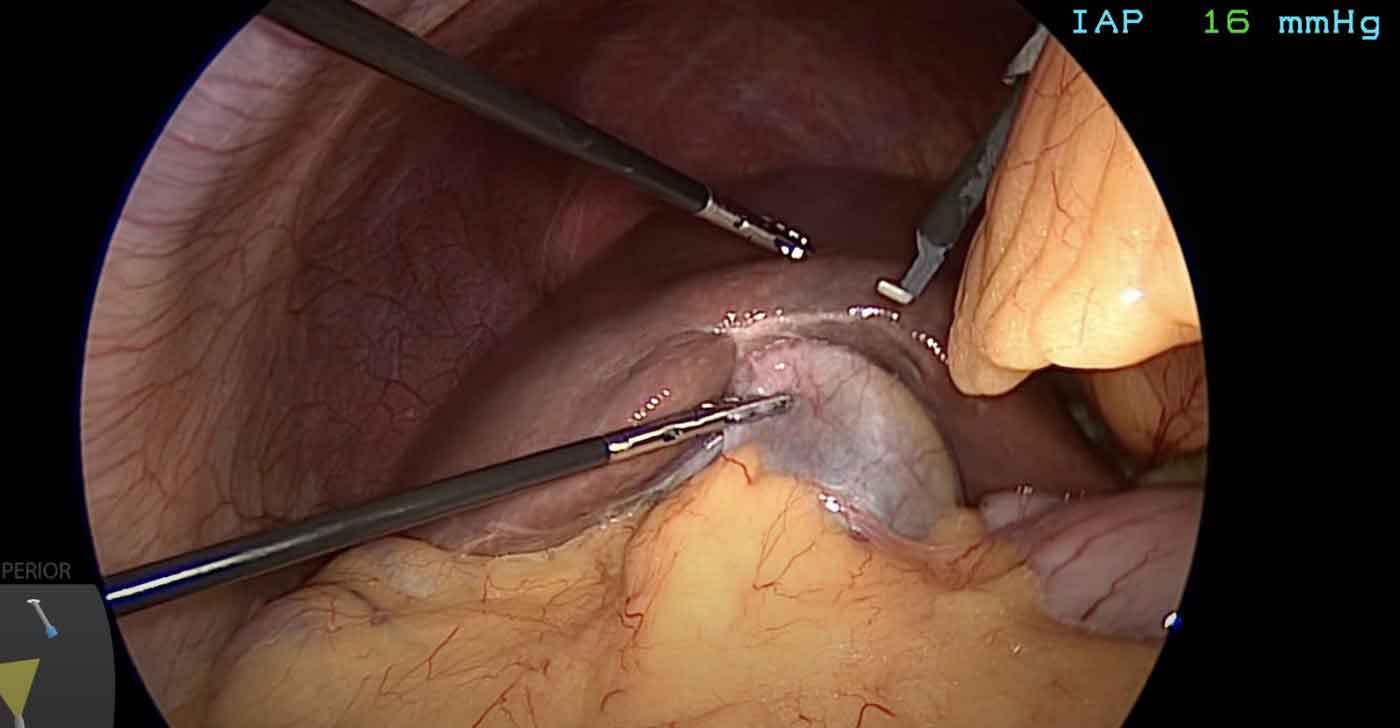

Performed through 3–4 small keyhole incisions (5–10 mm each) under general anaesthesia. A high-definition camera is introduced into the abdomen; fine instruments clip and divide the cystic duct and artery, then free the gallbladder from the liver bed. The gallbladder is extracted through one port.

Intraoperative laparoscopic view during cholecystectomy showing gallbladder dissection